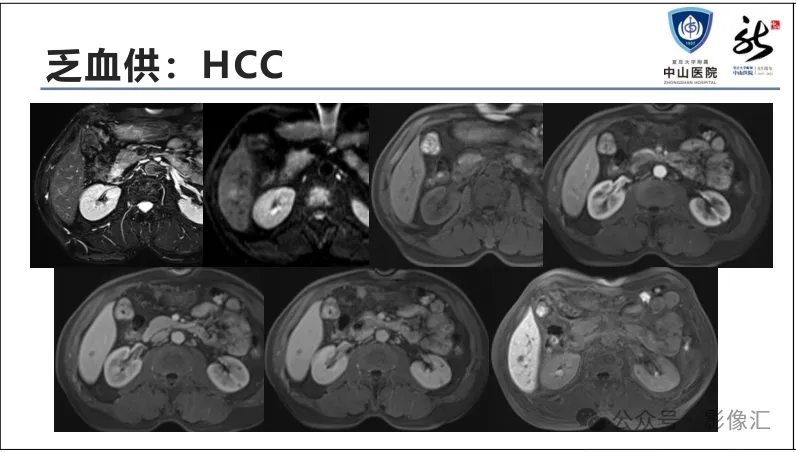

肝胆特异性对比剂增强肝胆图像判读方法与策略,课件来源于网络,作者复旦大学附属中山医院放射科饶圣祥教授。